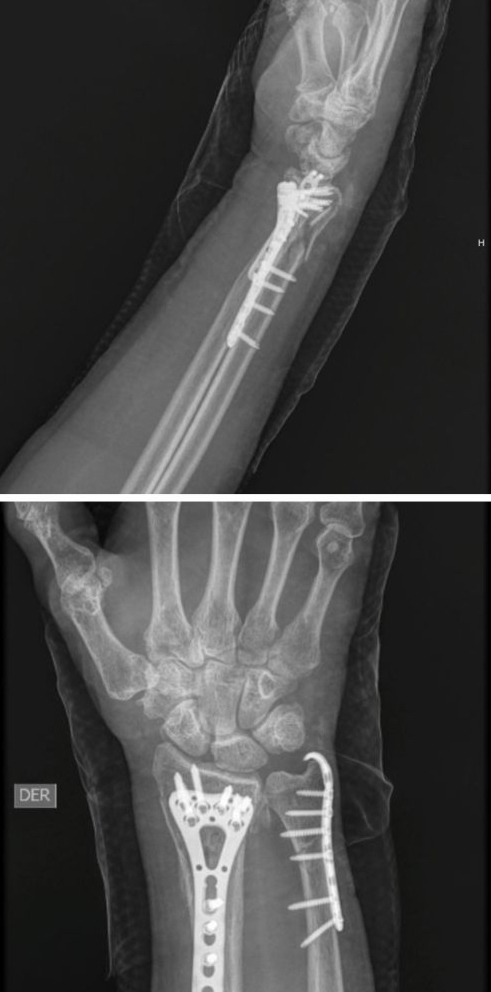

Después